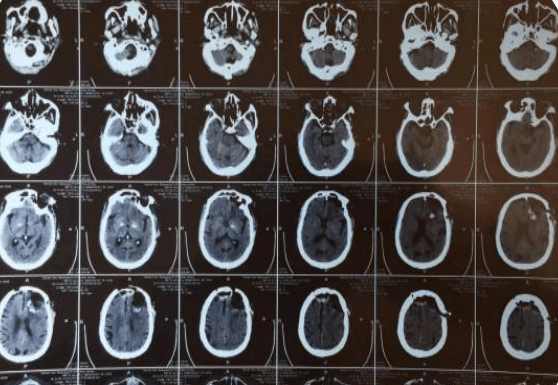

刀尖上的“舞者”,大脑中的“匠人”——记神外二科一例左侧额颞部占位患者的成功救治

约3个月前,赵大爷在我院查颅脑CT示:左侧额颞部占位,多考虑脑膜瘤;右侧额部皮下脂肪瘤,当时患者无明显症状,选择保守治疗,约一周前,患者出现意识混乱,头闷表现,家属为求进一步治疗,解决患者不适,提高患者生活质量,入院治疗。在刘小雷主任和游文良副主任医师的指导下,经过医护一体化协作模式的共同努力,为78岁高龄的赵大爷术前制定精准的手术方案,术中在病人家属的许可下,实施显微镜下颅内肿瘤切除术,经过精细的手术操作,手术顺利完成,并且一并切除右侧头皮脂肪瘤,颅内外问题一起解决,护理团队根据患者病情特点制定了护理计划及护理措施,密切观察患者瞳孔意识变化,肢体活动情况,观察患者生命体征变化,二十四小时出入量是否平衡,并详细的记录各项指标的变化,在护士专业而细致地看护下,术后五天,患者无任何不良反应,恢复良好,身体各项指标一切正常,无后遗症。在神经外科二病区医护团队的精心治疗和护理下,赵大爷病情日见好转,家属脸上也露出了久违的笑容。